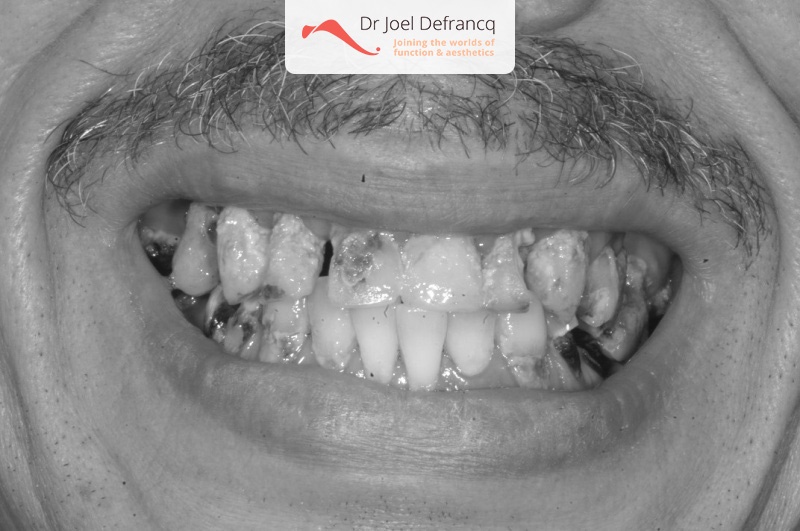

Deze patiënten komen het meest voor. Hun boventanden falen om verschillende redenen: esthetisch, functioneel, cariës, verwaarlozing, parodontitis, infecties allerlei. Zij willen dit proces niet overbruggen met een uitneembare prothese. Bovendien zijn de wangen niet ingevallen, aangezien de bestaande tanden nog altijd ‘volume behoudend’ zijn. Deze patienten zijn dan ook het eenvoudigst te behandelen: